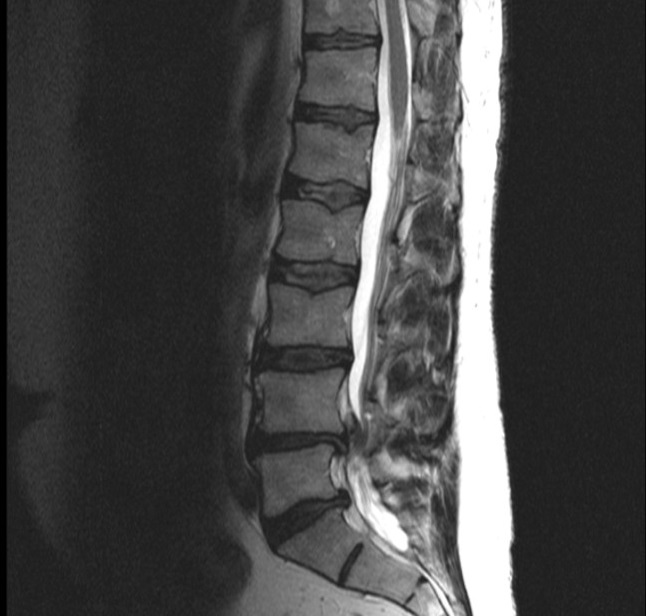

Spinalkanalstenose Wirbelsäule

Die Diagnose Spinalkanalstenose Wirbelsäule und Arthrose des rechten Iliosakralgelenks, die ich von zwei Spezialkliniken für Wirbelsäulen-Erkrankungen erhalten habe, war für mein Alter – ich bin 85 Jahre alt – nicht ungewöhnlich. Mein Problem war aber: ich konnte kaum noch 100 Meter weit ohne Schmerzen laufen. Man riet mir zu einer Operation der Wirbelsäule (L5/S1). Da ich um die Risiken einer solchen Operation weiß, zögerte ich.

Ich habe mich gegen die Operation Spinalkanalstenose entschieden. Deshalb bin ich froh, dass ich stattdessen zu Ihnen in die Praxis kam. Ich begann mit der Matrix-Rhythmus-Therapie, ergänzt durch Gymnastik und viel private Bewegung.